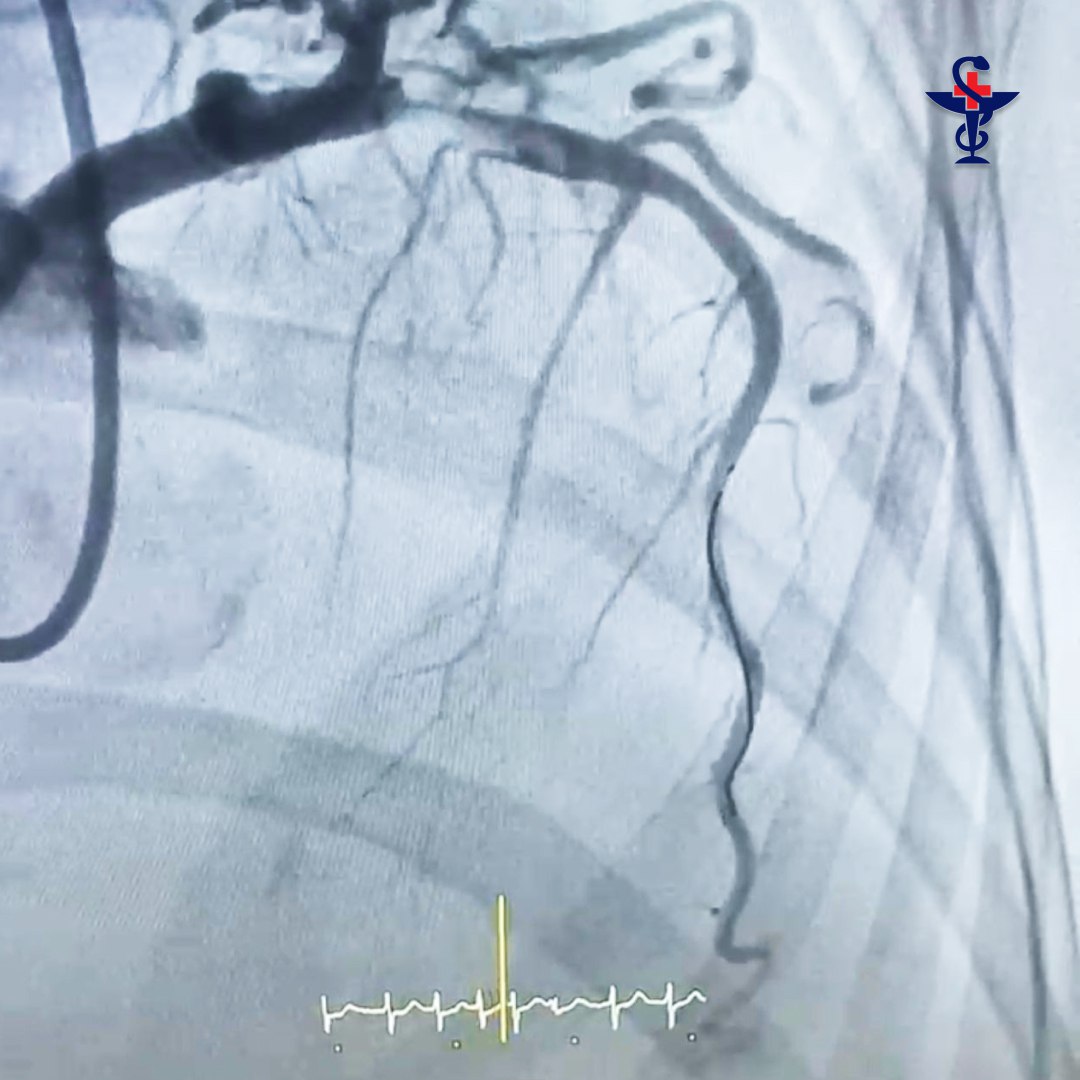

Приняв решение о проведении коронарографии и установки стента, врачи экстренно отправили больную в рентгеноперационную.

При контрастном исследовании проходимости сосудов сердца врачи обнаружили огромный тромб. Он практически полностью перекрыл просвет сосуда, что могло вызвать поражение сердца (инфаркт). В таком случае процент летального исхода возрастает в разы.

«По меркам сосудов сердца – это очень крупный и протяженный тромб, который мы успешно удалили, установили специальный стент (металлический каркас) и полностью восстановили проходимость коронарной артерии», – прокомментировала ход операции врач по рентгенэндоваскулярной диагностике и лечению Аделя Творогова.